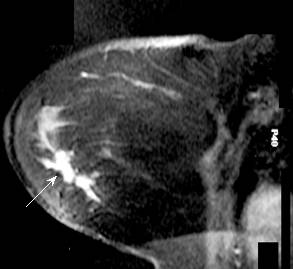

Breast MRI is playing an increasing role in imaging breast cancer see more pics Advanced stage: pic, pic, pic, pic, pic, pic, pic, pic, pic, pic, pic PET versus MRI here, here, here

breast cancer in left (go here) MRI may be useful in male breast cancer: see mammogram and MRI An MRI will show normal anatomy well (here) and is helpful in following women who have had surgery (here) and radiation (here). MRI of woman with previous cancer developed cancer in opposite breast (here) and woman with previous mastectomy with reconstruction developed recurrence in reconstructed breast (here) MRI is good for women have had previous breast implants (augmentation) go here |